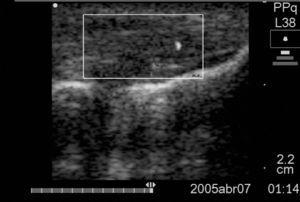

Ambos pacientes presentaban engrosamiento del tendón con pérdida del patrón fibrilar, zonas hipoecoicas y neovascularización en los tercios proximal y medio del tendón (fig. 1).

Figura 1 Corte longitudinal del tendón del caso 2 que muestra el engrosamiento, las áreas de hipoecogenicidad y la neovascularización del mismo.